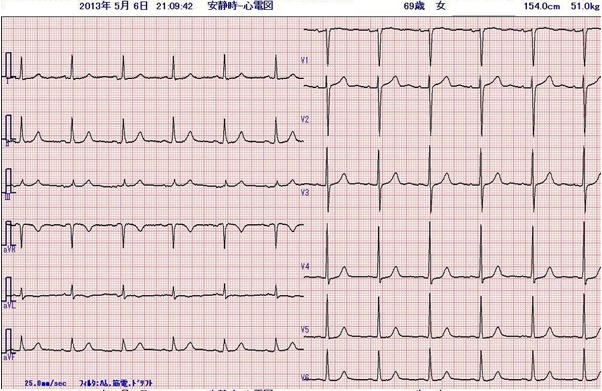

身体所見にその他、特記すべき異常所見はありません。その時にとられた心電図です。

これまで全く自覚症状のない人に左胸部痛が出現しています。吸気時に増強するという記載があり、非定型的ではありますが、まず急性冠症候群を考えます。冷汗と嘔吐という全身症状を伴っており、手術後の痛みや不安感だけでは説明できません。鑑別診断としては急性肺血栓塞栓症ですが、SpO2が正常であることから否定的です。緊急で施行した心エコー検査でも右室負荷の所見はみられませんでした。 心電図の所見は、Ⅰ、aVL、V4-6でT波の逆転、ないし平低化を認めます。術前にとられた心電図を示します。術前の心電図と比較すると、問題の心電図異常は新しく起きた変化であることが分かります。この所見からは、左室高位側壁、左室前壁から側壁にかけて心筋虚血がおこっている可能性があります。

患者さんの症状は急速に改善、処置が終了し病室に帰室されました。 心電図の経過をみると、

変化は明らかですが、その後、心筋逸脱酵素の上昇もなく心筋梗塞は回避できたと考えています。

心電図の経過